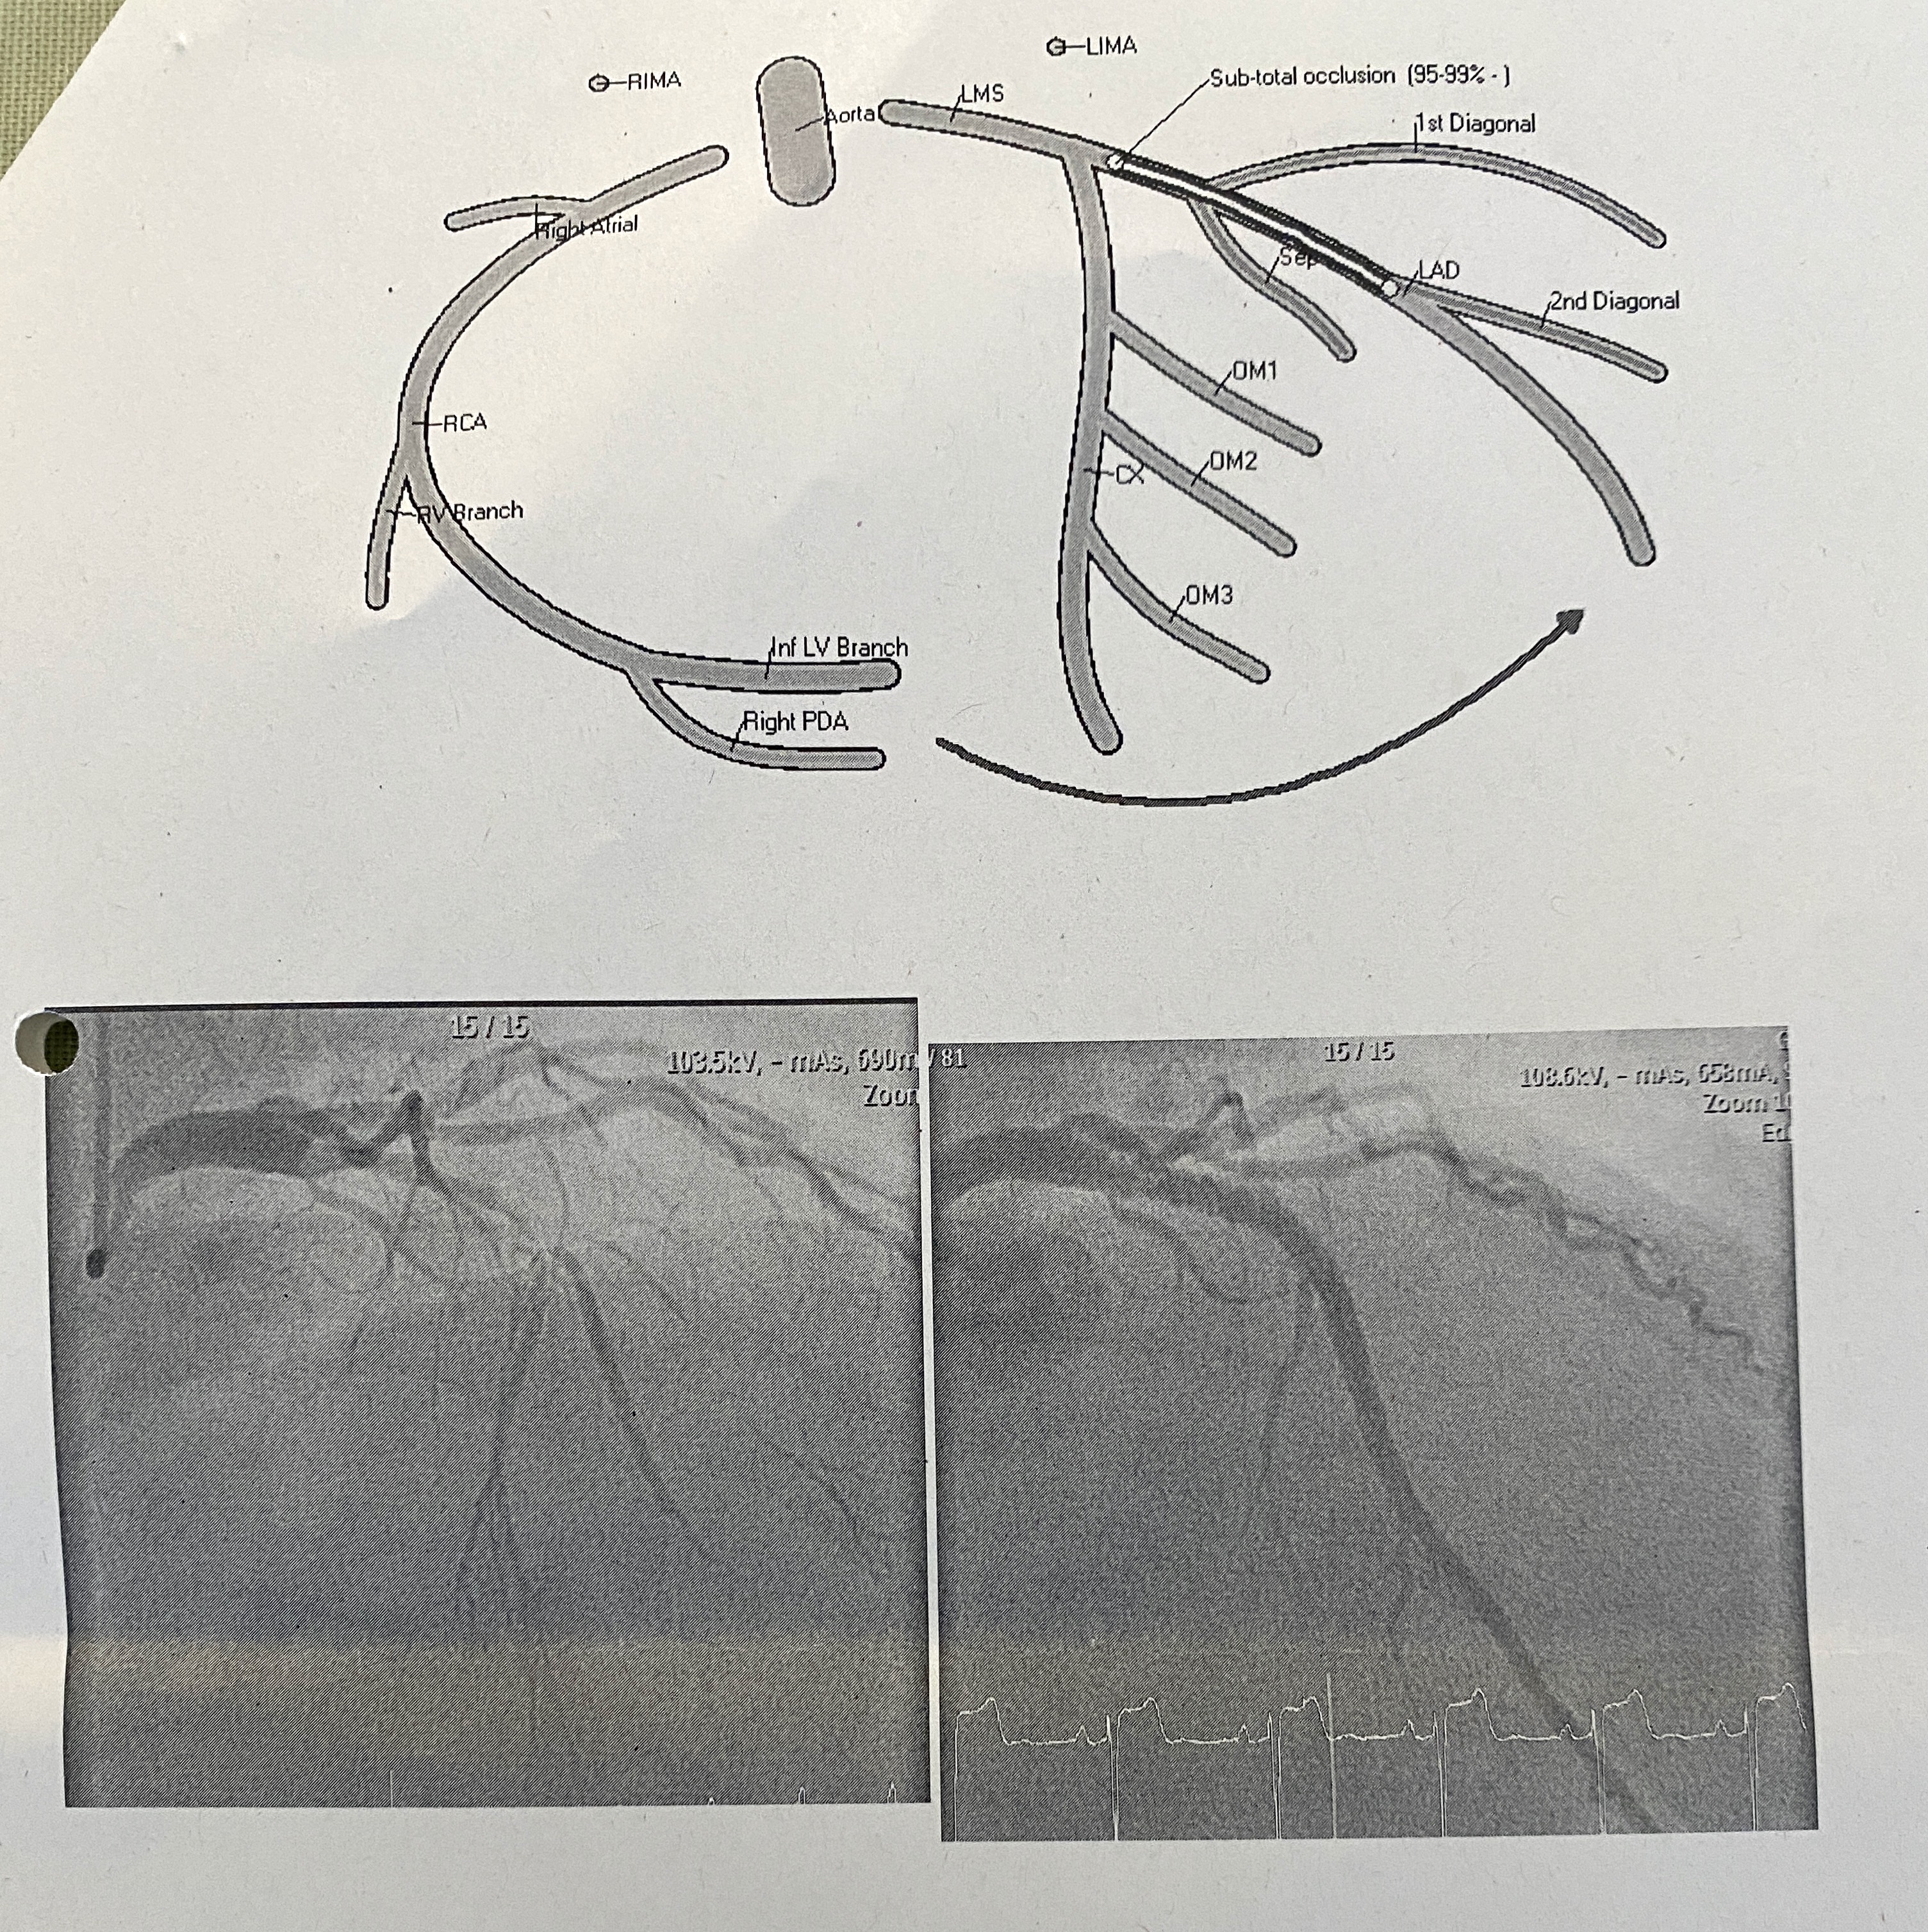

Angiogram przebiegł prawidłowo, ale stwierdzono, że moja lewa przednia zstępująca (LAD) tętnica wieńcowa jest w 95-99% niedrożna. Do tętnicy wprowadzono dwa stenty, aby ją udrożnić i utrzymać w stanie otwartym. Wszystko odbyło się w znieczuleniu miejscowym, co jest niesamowitym osiągnięciem. Trzy godziny później wyszedłem z sali operacyjnej z bardzo obolałymi rękami. Lewe zdjęcie poniżej przedstawia stan przed założeniem stentu, na którym barwnik pokazuje brak przepływu krwi, a prawe zdjęcie przedstawia stan po założeniu stentu.